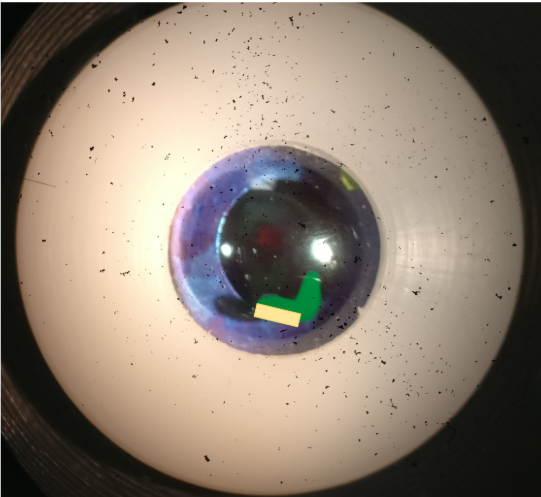

what slit lamp technique is being demonstrated on the model eye in this image

optic section

what slit lamp technique is being demonstrated on model eye in this image

parallelpiped